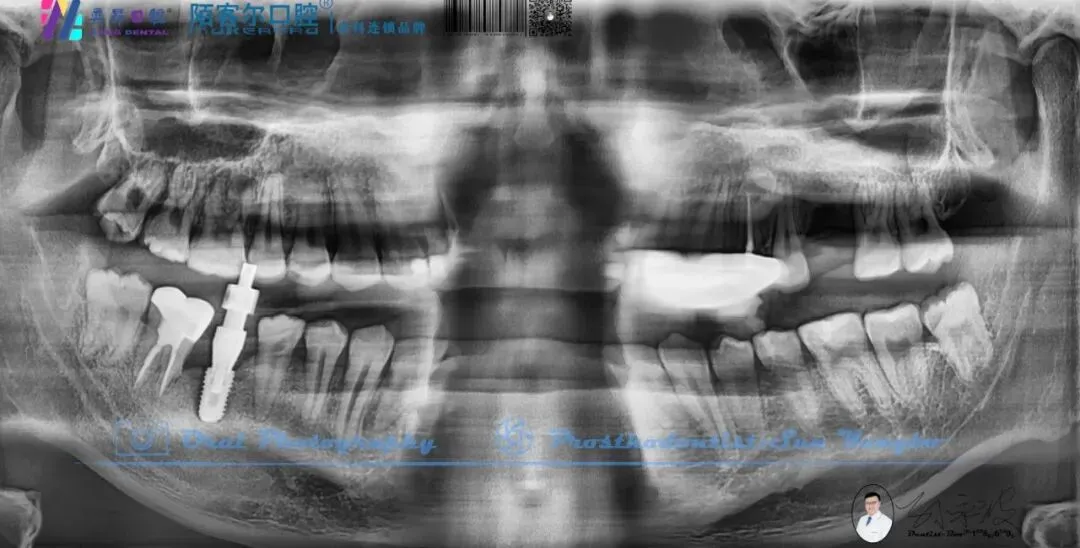

【深圳牙医-孙永波】病例16丨右下后牙单颗缺失种植修复